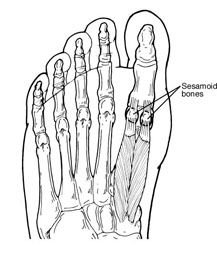

A sesamoid is a bone embedded in a tendon. Sesamoids are found in several joints in the body. In the normal foot, the sesamoids are two pea-shaped bones located in the ball of the foot, beneath the big toe joint.

A sesamoid is a bone embedded in a tendon. Sesamoids are found in several joints in the body. In the normal foot, the sesamoids are two pea-shaped bones located in the ball of the foot, beneath the big toe joint.

Acting as a pulley for tendons, the sesamoids help the big toe move normally and provide leverage when the big toe “pushes off” during walking and running. The sesamoids also serve as a weight-bearing surface for the first metatarsal bone (the long bone connected to the big toe), absorbing the weight placed on the ball of the foot when walking, running, and jumping.